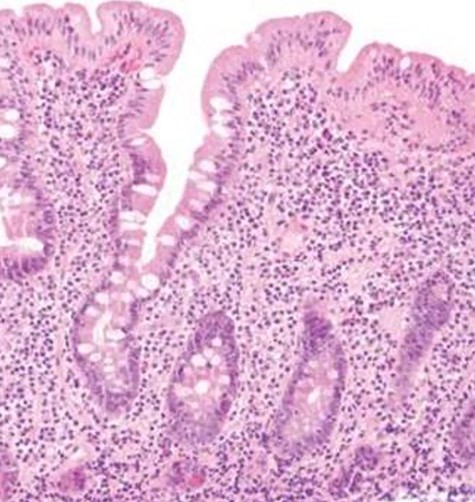

The decision to conduct a colonoscopy was undertaken to exclude inflammatory bowel disease and lower gastrointestinal (GIT) pathology. Colonoscopy revealed several adhesions throughout the pelvic organs (Fig. 1) and a biopsy revealed blunting of villi with subsequent crypt hyperplasia with no crypt abscesses, fistulas or granulomas (Fig. 2). There was a high clinical suspicion of celiac disease and laboratory confirmation was ordered. Lab results: positive immunoglobulin A (IgA) anti-tissue glutaminase 4.6 and immunoglobulin G (IgG) antideamidated gliadin peptide antibodies, IgA tTG 167 U/ml. Laparoscopy was performed as well to exclude any hidden etiologies including gynecological disorders that can lead to the adhesions but was not able to identify the cause.

Colonoscopy revealed several adhesions throughout the pelvic organs.

Biopsy revealed blunting of villi with subsequent crypt hyperplasia with no crypt abscesses, fistulas or granulomas.

Celiac disease is usually diagnosed based on two main pillars: the positivity of the serological tests and the pathological appearance of the intestinal biopsy. Serological testing involves the measurement of IgA anti-TGase—with the exclusion of other malabsorption diseases—which is positive in at least 98% of all cases of celiac disease on a gluten diet [3] as the first line of diagnosis because of its high sensitivity and high negative predictive values compared other non-sensitive tests [4]. IgG anti-gliadin antibodies have the highest sensitivity and specificity (Table 1) [4]. Positive serological testing should mandate duodenal biopsy and histopathological examination as a confirmatory test to ensure that patients are correctly diagnosed with the celiac disease before being subjected to a gluten-free diet for life. The hallmark of the histopathological picture of celiac disease is increased intraepithelial lymphocytes, crypt hyperplasia and villous atrophy (Marsh type 3) [5,6].